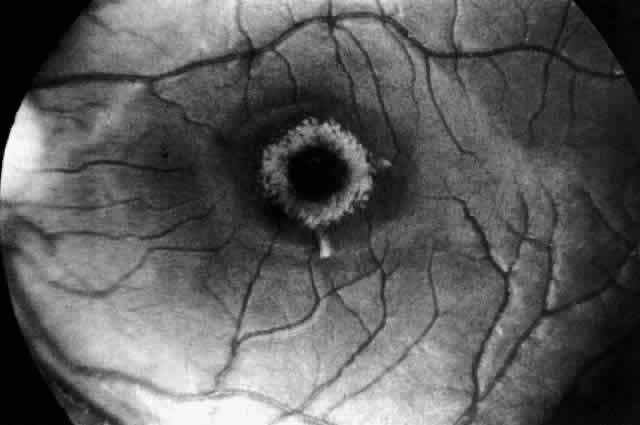

| Gaucher's disease is an autosomal recessive sphingolipidosis. The

disease is due to a deficiency of the enzyme ß-glucosidase, leading

to the accumulation of glucosylceramide in cells of the reticuloendothelial

system. The disease, first described by Gaucher in 1882,72 is characterized by hepatosplenomegaly and the presence of lipid-laden storage cells called Gaucher's cells in the bone marrow and organs. The disease is panethnic, although Gaucher's disease type I has a high prevalence among Ashkenazi Jews. A subset of' Gaucher's disease type III has been described with a high incidence in a Swedish isolate.73 CLINICAL MANIFESTATIONS. Three types of Gaucher's disease are distinguished: type II acute infantile neuronopathic, type III subacute juvenile neuronopathic, and type I chronic adult non-neuronopathic.74 Type II acute infantile neuronopathic Gaucher's disease is a unique neurovisceral disorder. Clinically it simulates infantile Niemann-Pick disease with the insidious onset of symptoms in early infancy, including failure to thrive, progressive hepatosplenomegaly, laryngeal stridor, and dysphagia. Anemia, thrombocytopenia, and leukopenia are present. Every infant with type II Gaucher's disease has evidence of severe and progressive CNS dysfunction before death. Signs of neurologic deterioration usually appear before 6 months and frequently before 3 months of age. A rather stereotyped neurologic syndrome has been observed in which hypotonia gives way to spastic weakness associated with a persistent retroflexion of the neck, with internal strabismus, seizures, and signs of pseudobulbar palsy. Motor skills and mental awareness are rapidly lost. The usual cause of death as the bulbar palsy worsens is bronchial aspiration and pneumonia. Type III subacute juvenile neuronopathic Gaucher's disease describes children and young adults who do not fit into either of the other two groups and whose illness is complicated by neurologic manifestations that differ from, and have a later age at onset and more chronic course than, those of the infantile form. Two clinical pictures are distinguished, depending on the age at onset of neurologic symptoms. The older patients,75–77 including two patients reported by Winkelman and co-workers,78 in whom symptoms began in late childhood, adolescence, or' early adult years, presented with similar neurologic syndromes, consisting of myoclonic epilepsy and supranuclear disorders of gaze. In some,75 including Winkelman's second patient,76 the gaze disorder was the more prominent; in others,76 myoclonic epilepsy was the most evident feature. Freedom from signs of cerebral involvement is the sine qua non for the diagnosis of type I chronic adult non-neuronopathic Gaucher's disease. Patients with this variant can have onset of the disease in childhood or in adulthood and a prolonged course. They manifest hepatosplenomegaly, anemia, thrombocytopenia, periods of bleeding, and pathologic bone fractures. Radiographic abnormalities of bone are present in 50% to 75% of patients. The most common sign is an Erlenmeyer flask deformity at the lower end of the femur due to expansion of the marrow cavity. OCULAR MANIFESTATIONS. The validity of two cited cases79,80 of a cherry-red spot in the retina of patients with Gaucher's disease has been questioned by Cogan and colleagues.81 In addition, one reported case of macular cherry-red spots in a 20-year-old woman believed to have Gaucher's disease, along with other similar cases, in retrospect now seems to have been an example of the cherry-red spot-myoclonus syndrome of sialidase deficiency.82,83 All three suspected Gaucher's disease cases antedated the biochemical means for establishing the diagnosis. In fact, it was not until 1965 that the enzyme assay for Gaucher's disease became available. To determine for certain the incidence of macular cherry-red spots in Gaucher's disease, Cogan and colleagues81 examined 42 enzymatically proven cases of the disease and reviewed the records of 9 others. In none was a cherry-red spot seen. In three patients with type III subacute juvenile neuronopathic Gaucher's disease however, the retina showed a unique retinopathy. The findings in Cogan's case 1 are described: “Both fundi showed discrete white spots randomly distributed in the posterior fundus, especially along the inferior vascular arcades (Fig. 8). The spots varied in diameter from just visible to approximately 0.1 mm and were situated in the superficial retina or on the surface of the retina. Several covered the retinal vessels. The disc and retinal vessels were normal.” The child, an 11-year-old boy, had normal acuity and a full field of vision by confrontation. He had presented at age 3 years with splenomegaly. Normal vision and similar retinal abnormalities were observed in a mildly mentally retarded 18-year-old woman (case 2) presenting with splenomegaly at age 1 year and in a 6½-year-old boy (case 3) noted to have hepatosplenomegaly in the first year of life. The patients in cases 1 and 3 had conspicuous supranuclear defects of eye movement. Japanese observers Yanagida, Matsumoto, Tokudo, and Hirose were the first to report the peculiar retinal spots in type III juvenile Gaucher's disease between 1950 and 1965. Their clinical reports in Japanese journals are referenced in Cogan and colleagues' paper.81 Type III juvenile neuronopathic Gaucher's disease is also associated with a distinctive supranuclear eye movement disorder affecting primarily horizontal gaze and only occasionally vertical gaze.75–78,84,85 The early defect in horizontal gaze involves the saccadic system, and the disorder mimics closely congenital ocular motor apraxia. To distinguish Gaucher's disease cases from benign congenital apraxia, it is essential to obtain the appropriate enzyme studies. NEUROPATHOLOGY. The liver, spleen, and long bones are the primary organs affected by the storage of glucosylceramide. The dominating precursors to the accumulation of glucosylceramide are derived from the normal turnover of leukocytes and erythrocytes, but other tissue cells also contribute. The highly cytotoxic substance glucosylsphingosine (the non-acyl derivative of glucosylceramide) is also stored in excess in the viscera in all types of Gaucher's disease and in the brain in the neuronopathic types, type II and III. This accumulation leads to cell death. Like the clinical features, the neuropathologic changes in patients with type II infantile neuronopathic Gaucher's disease are quite uniform. Nerve cell loss and neuronophagia involving the brain stem and deep cerebellar nuclei predominate, but the thalamus, basal ganglia, and spinal cord are also affected. Such neuronal destruction is diffuse and, except for oculomotor abnormalities and dysphagia, causes no localizing signs. Perivascular nodular collections of Gaucher's cells are found in the brain, invading the meninges and in Virchow Robin spaces. Gaucher's cells have a unique appearance. The cytoplasm has a wrinkled tissue-paper appearance because of interwoven fibrils contained within it. Under the electron microscope the cells contain large lysosomes filled with tubular profiles. These cells are distinct in their appearance and differ markedly from foam cells seen in other lipidoses.86 A pathologic study of two siblings with neuronopathic Gaucher disease and supranuclear upgaze and horizontal gaze palsies has demonstrated similar widespread involvement of the cortex, cerebellum, and spinal cord. The midbrain, pretectal region, oculomotor and red nuclei, superior colliculus, substantia nigra, and reticular formation were all involved. In the pons, the paramedian reticular formation showed pathologic change, as did the abducens and superior vestibular nuclei.78 An electron microscopic study of Gaucher's cells in the eye in type III juvenile neuronopathic disease is reported from Japan by Ueno and associates87,88 who noted white spots in an arcuate pattern in the fundi of an 8-year-old Japanese boy. At autopsy the retinal spots corresponded to polymorphonuclear giant cells within and on the surface of the retina. These cells were large and stained positively for glycolipid and acid phosphatase. DIAGNOSTIC TESTS. The disease is confirmed by demonstration of a deficiency of glucocerebroside-ß-glucosidase in leukocytes and fibroblasts. In spite of the range of biologic expression, the same enzyme is deficient in all three types of the disease. Moreover, lack of complementation in cell fusion studies strongly suggests that these forms of Gaucher's disease represent allelic mutations at the same gene locus.89 There is a rare variant of Gaucher's disease clinically similar to adult non-neuronopathic disease type I but in which glucocerebroside-ß-glucosidase activity is normal. In this variant the defect is believed to be due to absence of the A activator protein.90 Prenatal diagnosis is available for all three types. It is seldom requested for type I Gaucher's disease. |